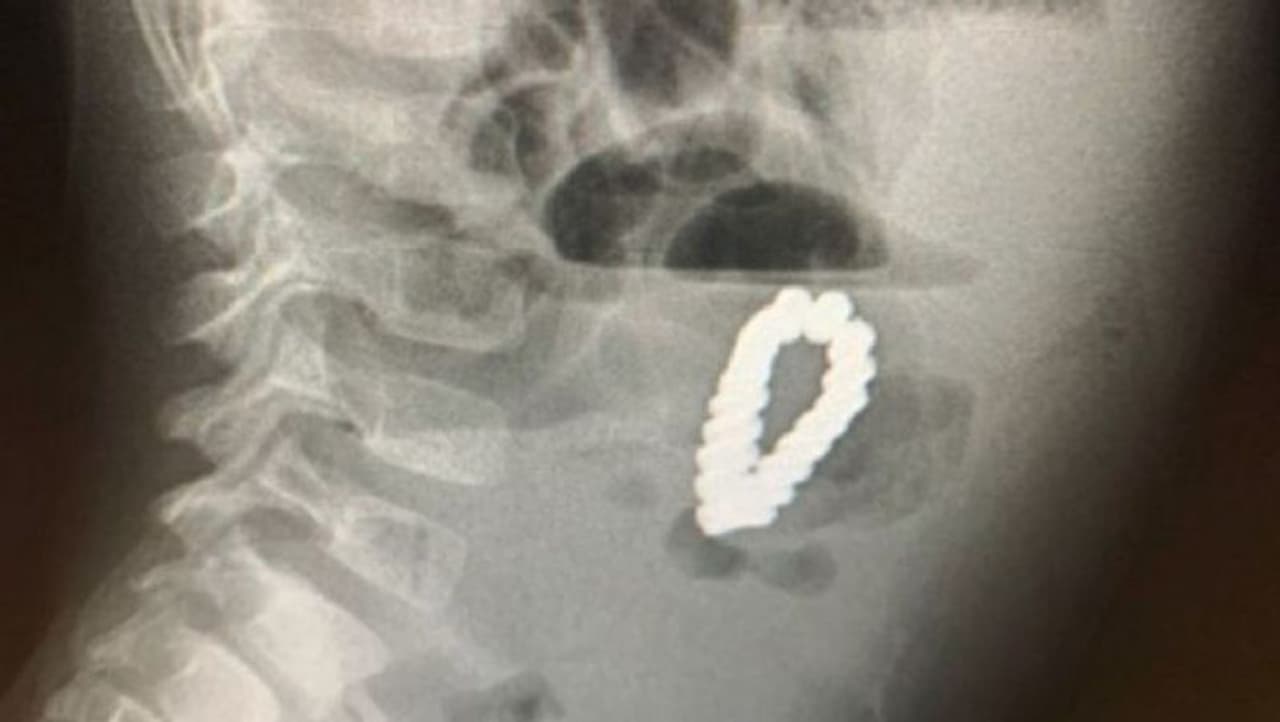

சிறுவனின் வயிற்றில் இரும்பு ப்ரேஸ்லெட் இருப்பதாய் கண்டிபிடித்தனர். மருத்துவர்கள் பரிசோதனைக்குப் பிறகு உறுதிசெய்தனர். பின்னர் அவர்கள் அவனது வயிற்றில் இருந்த ப்ரேஸ்லெடடை அகற்றினர்.